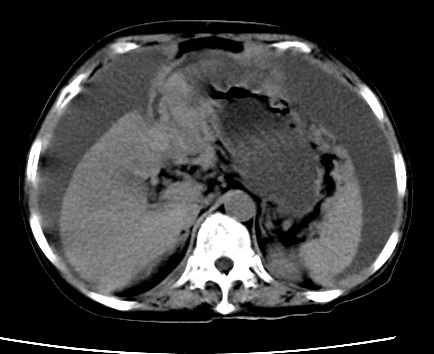

既往5年前卵巢癌行子宫及附件切除,右乳癌术后一年,考虑腹膜转移?

大量腹水,考虑腹膜转移。肝脏低密度灶。1囊肿,2转移。

1)结合病史,考虑腹膜及网膜转移瘤。2)肝脏多发性低密度灶,不排除转移瘤。3)大量腹水。

考虑卵巢癌行子宫术后复发,并肝、腹腔 、大网膜转移可能性大。

大量腹水。